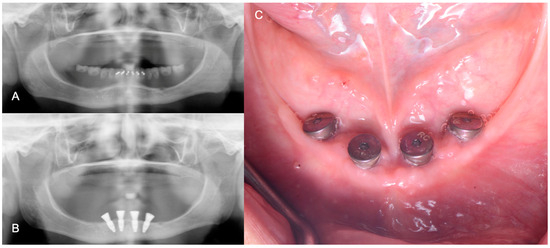

2. Materials and Methods